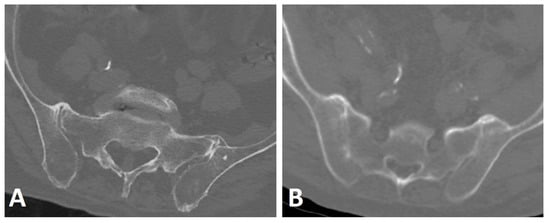

Bridging osteophytes in DISH are located along the anterolateral aspect of the vertebral bodies, most commonly involving the seventh through eleventh thoracic vertebrae [36,51,52]. These osteophytes are mostly detected on the right side of the spine, leading to the hypothesis that the pulsating, left-sided descending aorta inhibits new bone formation on the left [29,53]. Providing further validation of this hypothesis on the protective effect of the aorta, a previous study demonstrated the same effect in patients with the right-sided aorta, in which the majority of osteophytes were located contralateral to the descending aorta’s location (Figure 5) [25]. Moreover, a study on the location of syndesmophytes in subjects with AS reported the same reduced frequency of syndesmophytes at the vertebral rim near the aorta [54].

Figure 5.

Axial CT images of two patients with thoracic DISH (not shown). (A) left-sided and (B) right-sided aortas with an anterior osteophyte located contralateral to the aorta’s position.